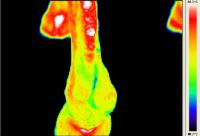

Temperaturwert = Farbwert | temperature value = colour value |

Walzertraum - Pferd nach Sehnen-OP - Horse after tendon operation